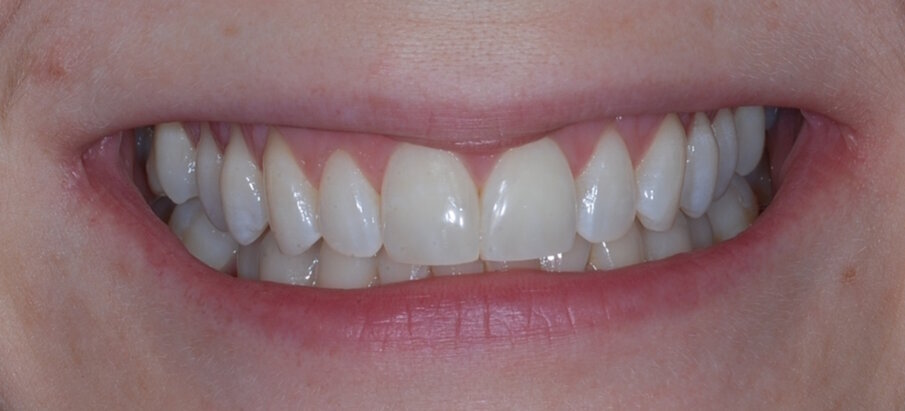

Fig. 1: Pre treatment anterior

Fig. 15: Post treatment anterior